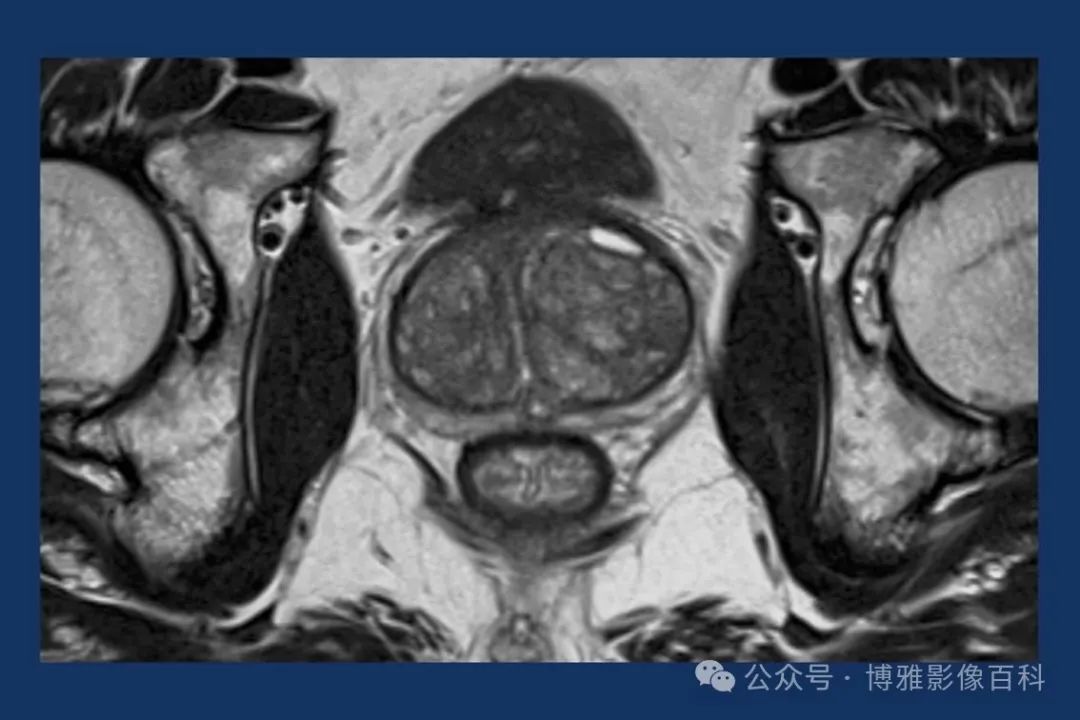

前列腺良性增生患者的轴向T2 图像,其他方面正常。外周带是一薄层均匀的高信号,边界清晰连续性的低信号包膜。移行带通常表现为不均匀中等信号,病灶被边界清楚的BPH良性前列腺增生结节所取代。精囊具有均匀T2高信号。未见淋巴结肿大。